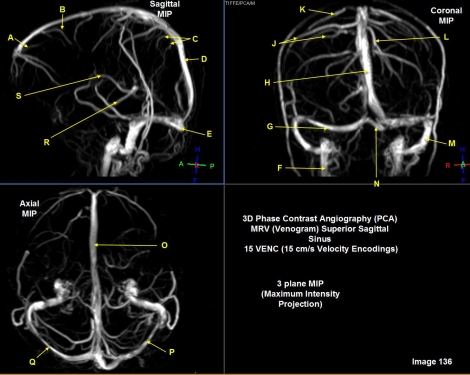

letter A in image 136 is pointing to

anterior frontal vein

letter B in image 136 is pointing to

posterior frontal vein

Letter C in Image 136 is pointing to:

Parietal veins

Letter D in Image 136 is pointing to:

Superior sagittal sinus

Letter E in Image 136 is pointing to:

Torcular herophili

Letter F in Image 136 is pointing to:

Internal jugular vein

letter G in image 136 is pointing to:

right transverse sinus

Letter H in Image 136 is pointing to:

Letter J in Image 136 is pointing to

right parietal veins

Letter K in Image 136 is pointing to:

vein of trolard

Letter L in Image 136 is pointing to:

left parietal veins

Letter M in Image 136 is pointing to:

Left sigmoid sinus

Letter N in Image 136 is pointing to:

Letter O in Image 136 is pointing to:

Letter P in Image 136 is pointing to:

Left transverse sinus

letter Q in image 136 is pointing to

Letter R in Image 136 is pointing to:

Basal vein/rosenthal vein

Letter S in Image 136 is pointing to:

Internal cerebral vein